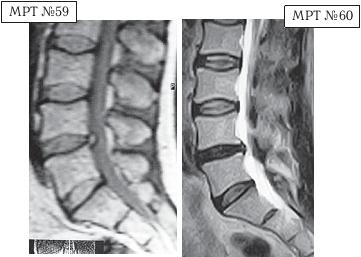

Пожалуй, приведу один пример из своей практики, чтобы вы понимали процессы, которые развиваются при соответствующей патологии в организме, если её лечить только медикаментозно. Но вначале поясню некоторые моменты по поводу снимков МРТ. При МРТ-обследовании используют режимы сканирования (Т1- и Т2-), которые позволяют получать основные типы взвешенности изображений (ВИ). В режиме Т1-ВИ структуры, содержащие воду (к примеру та же цереброспинальная жидкость (ликвор)), выглядят на снимке как более тёмные участки (МРТ № 59). А в режиме Т2-ВИ цереброспинальная жидкость (ликвор) и другие жидкости с низким содержанием белка выглядят на снимке как яркий (светлый) участок (МРТ № 60).

На МРТ № 59 от 23.04.2005 наблюдается грыжа межпозвонкового диска в поясничном отделе позвоночника в сегменте LIV-LV.

На МРТ № 60 того же самого пациента от 06.11.2009 наблюдается протрузия межпозвонкового диска в сегменте LIV-LV, частично компенсированная спондилёзом. Данный пациент прошёл лишь курсы медикаментозной терапии. Методы лечения мануальной терапии и вытяжения позвоночника не применялись.

Действительно, грыжа межпозвонкового диска на втором снимке (МРТ № 60) отсутствует. Однако надеюсь вы заметили, что грыжа межпозвонкового диска хоть и компенсировалась спондилёзом, но стеноз спинномозгового канала как был, так и остался. То есть, за это в некотором смысле потерянное время произошло усугубление дегенеративных процессов, как в данном сегменте, так и в других сегментах. Не удивительно, что самочувствие этого пациента за последние два года значительно ухудшилось. Поэтому он вынужден был вновь искать другие центры лечения опорно-двигательного аппарата и таким образом обратился ко мне в клинику.